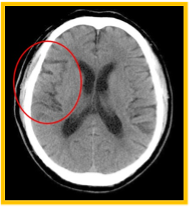

体を透過したX線を多方向から収集し、コンピューター処理によって輪切り(断層)画像を作成する装置です。脳、肺、肝臓、膵臓、血管などの臓器や、小さい病変も鮮明に描出できます。病変の正確な位置や大きさを三次元(3D)に把握することが可能で特にがんの発見、脳卒中、外傷による骨折や内臓の損傷など迅速で精密な診断が求められる場面で不可欠な検査です。

MRI検査には20~60分の時間を要します。脳内腫瘍をはじめ、感覚などの神経系、手足の関節、その他腫瘍が疑われる部位の軟部組織の描出を得意としています。また、造影剤を使用せずに脳や頸部の血管を描出することも可能です。さらに、CTに比べて脳梗塞の診断に優れており、より早期かつ正確な評価が可能です。

CTは脳出血の有無確認に優れ、検査時間が短く救急で有用ですが、発症直後の脳梗塞は変化が分かりにくい場合があります。MRIは早期の脳梗塞を白く明瞭に描出でき、病変の範囲や状態をより正確に評価できます